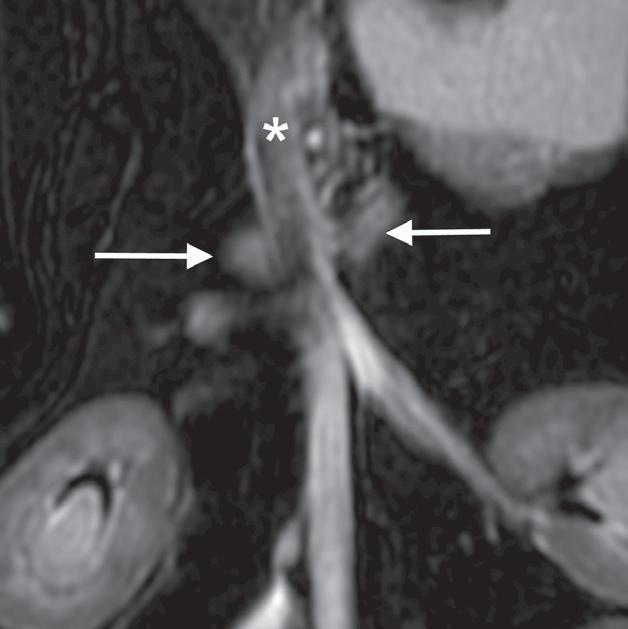

Rycina

3.2.8. Podwichnięcie kręgów szyjnych ze złamaniem wyrostka stawowego (pies) TK i MR

Badania wykonano u 5-letniej samicy mieszańca w typie teriera, która została pogryziona w okolicy szyjnej przez większego psa tego samego dnia, w którym wykonano badania. Podczas wizyty u psa zaobserwowano deficyty neurologiczne z neuroanatomiczną lokalizacją w obrębie C6–T2. Radiogramy przeglądowe ukazały grzbietowe podwichnięcie kręgu C7 względem C6 oraz zwężenie przestrzeni międzykręgowej C6–C7 (a – grot strzałki). Podobne zmiany uwidoczniono na obrazach TK w projekcji strzałkowej i 3D (b, f – grot strzałki). Dodatkowo stwierdzono wieloodłamowe złamanie z przemieszczeniem prawego doczaszkowego wyrostka stawowego kręgu C7 (c–e – strzałka). Dla porównania przedstawiono prawidłowy lewy wyrostek stawowy (f – strzałka). W badaniu MR przestrzeń międzykręgowa C6–C7 była zwężona i wykazywała obniżoną intensywność sygnału w obrazach T2-zależnych (i – strzałka), a przemieszczony materiał dyskowy znajdował się w prawej dobrzusznej części kanału kręgowego (g, h – grot strzałki). W obrazach występują cechy ucisku na rdzeń kręgowy (g–i) oraz zwiększona intensywność sygnału w sekwencji T2-zależnej w obrębie rdzenia na poziomie C6–C7 (h, i), co wskazuje na jego uszkodzenie wewnętrzne. Materiał dyskowy został chirurgicznie usunięty z kanału kręgowego, a podwichnięcie zredukowano i ustabilizowano operacyjnie